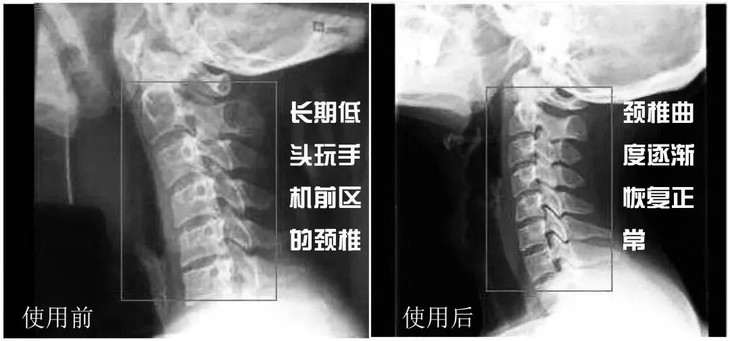

颈椎病对我们最直观的影响

就是会改变人体的体态

驼背、高低肩、富贵包以及颈纹

等等多种问题同时出现

像平时有脖子前倾、富贵包情况的朋友,睡这种贴合颈椎的枕头,也可以起到一个缓解的作用。

不仅能舒缓颈椎疼痛,还可以防止“颈椎反弓”,枕着它睡觉一夜安眠,做一个舒适的美梦~